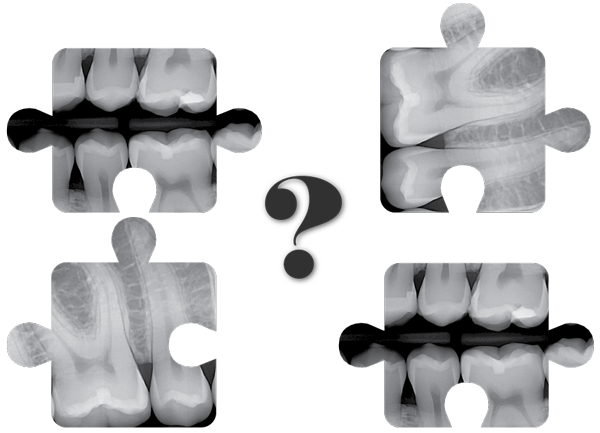

How DentiMax' dental sensors work when it comes to capturing dental xrays in Eaglesoft.